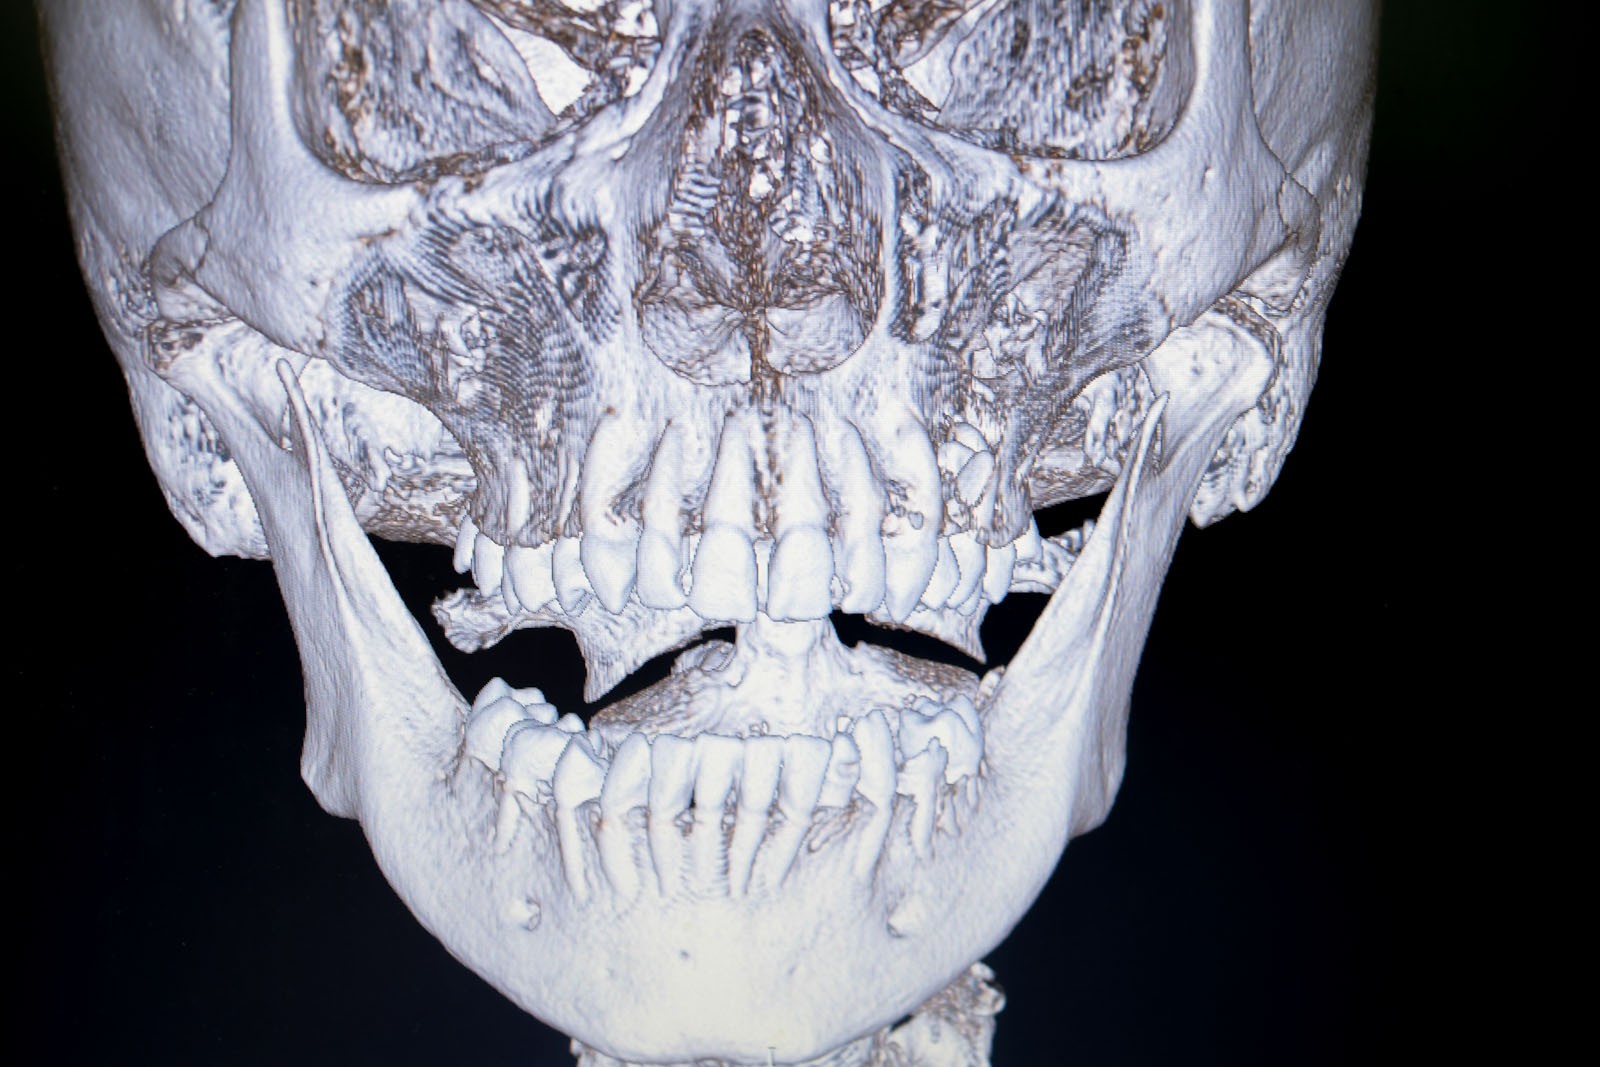

Narząd żucia stanowi funkcjonalną jedność z całym organizmem i nazywany jest układem stomatognatycznym. Zęby są jedynie częścią tego układu, w skład którego wchodzą kości twarzoczaszki, tkanki miękkie oraz układ nerwowo-naczyniowy.

Metoda Gerbera jako punkt wyjścia dla analizy traktuje staw skroniowo-żuchwowy. W relacji do jego funkcji bierze pod uwagę pozostałe ogniwa układu stomatognatycznego. Staw skroniowo-żuchwowy jest działającym synchronicznie symetrycznym elementem anatomii twarzoczaszki, który pozwala na otwieranie ust i funkcje z tym związane. To staw o złożonej budowie, w jego skład wchodzą: dołek stawowy kości skroniowej, który stanowi panewkę stawową, wyrostek kłykciowy, krążek stawowy i torebka stawowa. Krążek zbudowany jest z chrząstki i dzieli jamę stawową na dwie części: górną i dolną. Podczas ruchów opuszczania żuchwy (otwierania ust) krążek stawowy przesuwa się do przodu i dołu. Wraz z krążkiem przesuwa się wyrostek kłykciowy głowy żuchwy po obu stronach. W ruchu przywodzenia żuchwy (zamykania ust) krążek stawowy i wyrostek kłykciowy żuchwy wracają na swoje miejsce do pozycji wyjściowej. Stawy są sprzężone ze sobą czynnościowo (ruch następuje równocześnie w obu stawach) i anatomicznie (łączy je trzon kości żuchwy), stąd też nieprawidłowe asymetryczne obciążenia stawów są najczęstszą z przyczyn zaburzeń narządu żucia.

Utratę każdego zęba należy uzupełnić możliwie jak najszybciej, ponieważ nawet pojedyncze braki zębowe mogą prowadzić do niekorzystnych następstw dla całego układu żucia. Po utracie zęba dochodzi do zaniku kości wyrostka zębodołowego w wyniku braku jej osiowego obciążenia siłami żucia. Dochodzi do przemieszczania się zębów pozostałych w sąsiedztwo powstałej luki. Mogą się one przechylać, obracać i wysuwać z zębodołu bez względu na to, czy dotyczy to łuku górnego czy dolnego. Ruchy zębowe uzasadnia ich fizjologiczne dążenie do kontaktu ze sobą. Stąd braki zębowe w przeciwstawnym łuku deformują zgryz. Proces ten opisywany jest jako objaw Godona.

W rezultacie prowadzi to do utraty kolejnych zębów. Następstwa postępujących braków zębowych prowadzą do powstania zaburzeń funkcji stawów skroniowo-żuchwowych. Mogą objawiać się trudnościami w rozwieraniu szczęk, bólami mięśni twarzy i głowy w okolicach skroni, jak również prowadzić do zaburzeń trawiennych. Poza funkcją istotna jest również estetyka. Widoczne w uśmiechu braki zębowe, skrócenie dolnego odcinka twarzy, zapadnięcie się warg czy tworzenie się zmarszczek w okolicy ust to tylko niektóre z następstw towarzyszących ubytkom uzębienia. Uzupełnianie braków zębowych przywraca podstawy fizjologii jamy ustnej, ponieważ zęby jako zespół funkcjonują prawidłowo tylko w komplecie.